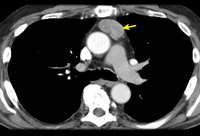

Tomografia computadorizada (TC) do tórax mostrando timoma em estádio III de Masaoka-Koga com comprometimento da parede torácica anterior e invasão da região medial do pulmão esquerdo

Do acervo de Cameron Wright, MD; usado com permissão